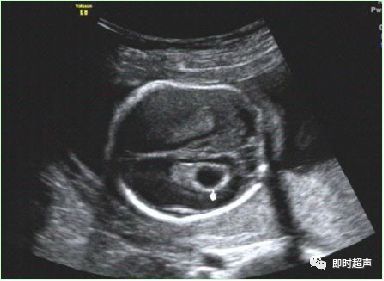

五、心室内强光斑(EIF)

心室内强回声光斑或心内灶性强回声

胎儿心室强光点指直径为1~6mm的斑状、灶状或条索状的结构,其回声强度与周围骨结构接近,可为单发,多发,以左室乳头肌处最常见,是妊娠期较常见超声表现。随孕期增加逐渐减弱,最迟在1岁内消失。

心室内腱索增厚而形成的强回声反射;乳头肌中央矿物质的沉积、钙化,这可能是乳头肌内冠状动脉末梢分支早期缺血性改变。

病理学可见乳头肌处的微钙化灶,可能与胎儿染色体异常有关。大多数的研究报道单纯性的心室强光点常无临床意义。

超声检查胎儿心室强光点临床意义

✔ 低风险胎儿如单独出现EIF而无其他异常超声表现时,临床意义不大,可超声随访,不必进一步做有创性检查。

✔ 高风险胎儿即使单独出现EIF,其染色体异常的风险也增加,建议遗传咨询,结合临床多因素谨慎处理。

✔ 低风险组胎儿检出EIF,同时合并有多项其他超声软标志时,其染色体异常的风险增加。

✔ 大多数的研究报道单纯性的心室强光点常无临床意义,超声检查所见的胎儿心脏发育过程中的一种变异。